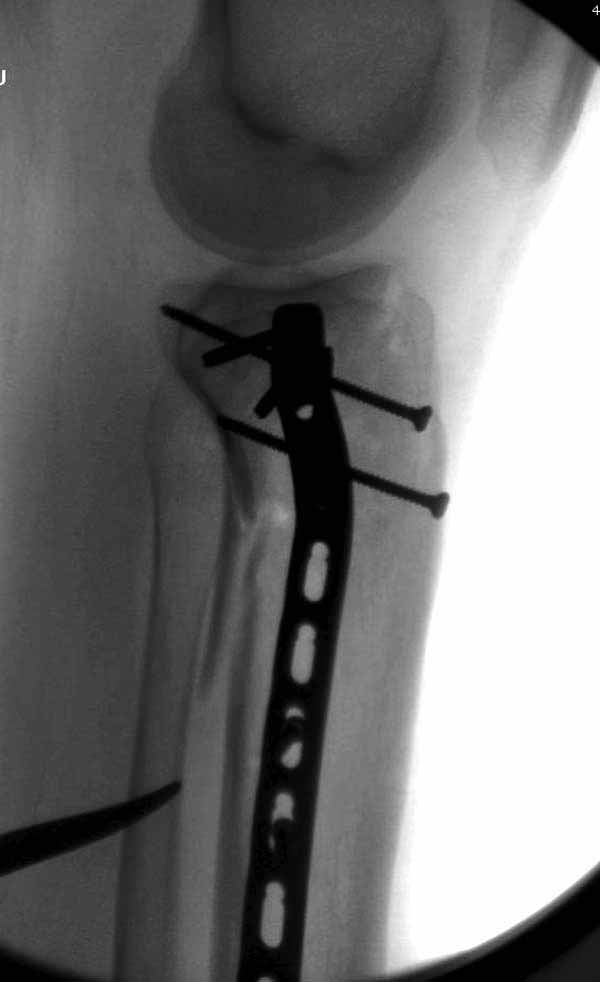

Удобно аппаратом Илизарова или интрамедуллярным гвоздем. Гвозди не так сложно, как пугают, тем более Александр готов помощь с методичкой. Сперва надо установить компрессирующие шурупы на мыщелки. Давно отказались в пользу 3.5-4.0 мм кортикальных вместо толстых спонгиозных, потому что не доказаны преимущества толстых шурупов. Тонкие шурупы в субхондральной зоне смотрятся намного элегантнее, чем толстые 6.5.

Это мероприятие превращает перелом в простой диафизарный, который легко можно фиксировать гвоздем. Шурупы надо установить сзади предполагаемого места введения гвоздя.

В приложении этапы фиксации Both Column Fx и пластиной Synthes для плеча при переломе медиального мыщелка.